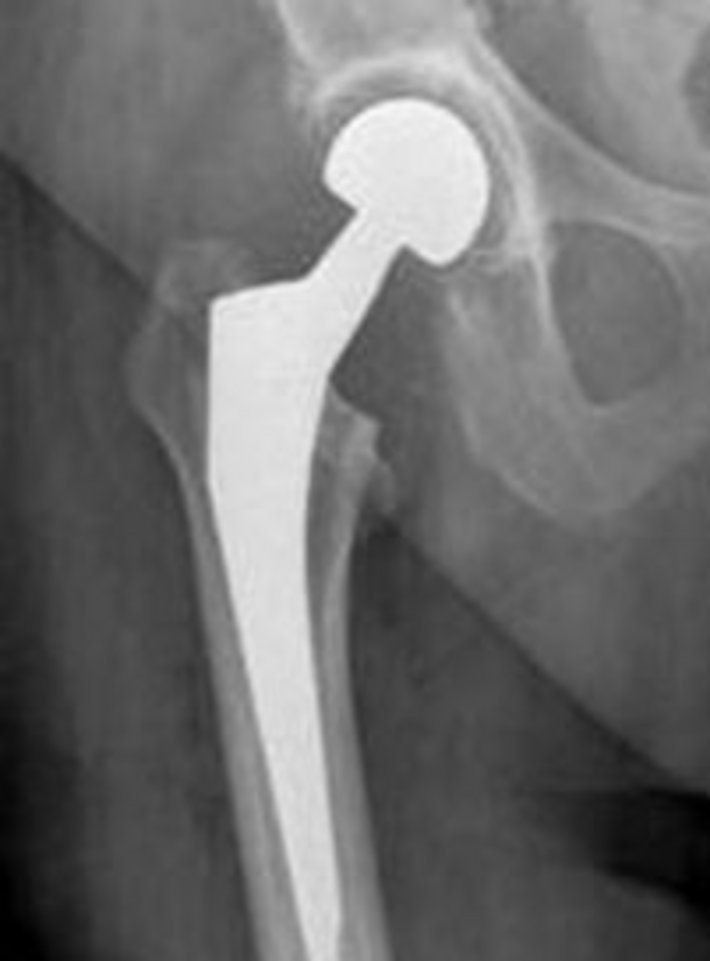

Es gibt verschiedene Modelle von künstlichen Hüftgelenken. Bei der Wahl der Prothese und ihrer Verankerung spielen unter anderem der Gesundheitszustand des Patienten, seine Knochenqualität und seine körperliche Aktivität eine Rolle. Ziel einer jeden Erstoperation ist es möglichst viel vom eigenen Knochen zu erhalten und die ursprüngliche Anatomie weitestgehend wiederherzustellen. Die Kunstgelenkmodelle, die dieser Aufgabe am besten gerecht werden, istdie Kurzschaftprothese. Diese können bei Patienten mit einem Lebensalter von unter circa 60 Jahren und guter Knochenqualität eingesetzt werden.

Das häufigste künstliche Hüftgelenk

Das künstliche Hüftgelenk, die sogenannte unzementierte Hüftendoprothese (Hüft-TEP), wird weltweit am häufigsten implantiert. Es besteht ein sehr langer Erfahrungszeitraum und man kann in den meisten Fällen eine hervorragende Funktion vorhersagen. Das Kunstgelenk wird in den Hüft- und Oberschenkelknochen passgenau eingebracht. Sowohl Gelenkspfanne als auch Hüftkopf werden dabei ersetzt. Sollte eine Knochenschwächung durch Osteoporose vorliegen, können die Gelenke mit Knochenzement sicher verankert werden (zementierte Hüftendoprothese).